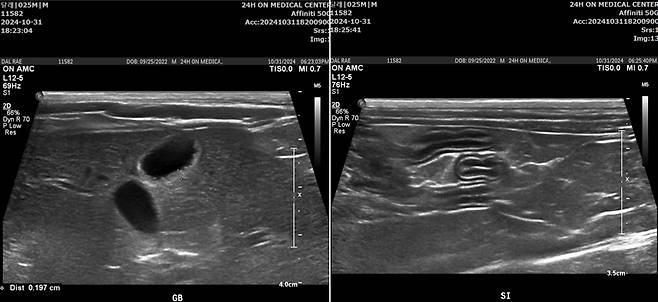

달래는 복부 초음파 검사에서 담낭과 총담관의 벽이 심하게 비후해지고, 소장 주위 림프절, 복막에도 염증 소견이 함께 관찰됐다. 염증성 장병증도 함께 의심되는 상황이었다. 다행히 췌장 쪽은 특이 소견이 발견되지 않았다.